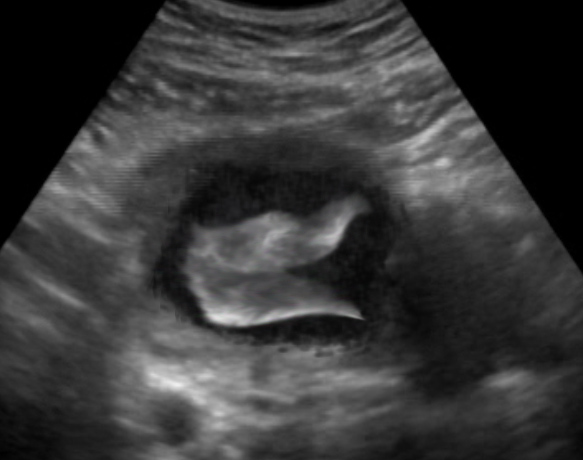

Attachment 28697Attachment 28698

SaoirseMae, 19 weeks Face, and fins. ;)

Tails by Linzee777 on DeviantArt. Photomanip and Baby by me. ;)